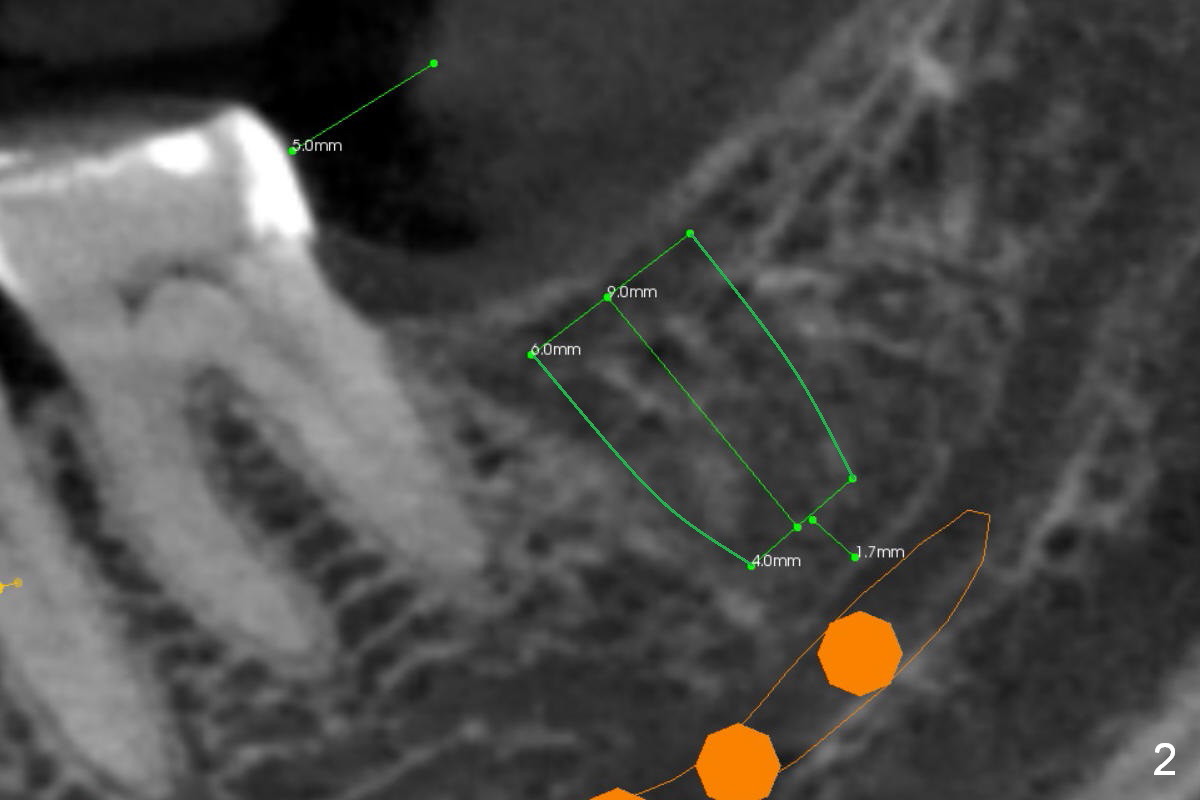

A 65-year-old woman is afraid of dentistry. After loss of the tooth #18 (Fig.1 with upper RPD), she feels necessary to have an implant (Fig.2). Since the ridge is wide (Fig.3), a flapless approach is adopted (Magic Split, measure the diameter of its handle). After 1.6 mm pilot drill (9 mm stopper) and Marking Drill (know the diameter of the large portion), use 4.8 mm Magic Drill (spacer set 2.5 mm, stopper 11 mm). Try in 5.5x9 mm dummy implant and most likely 6x9 mm definitive one.